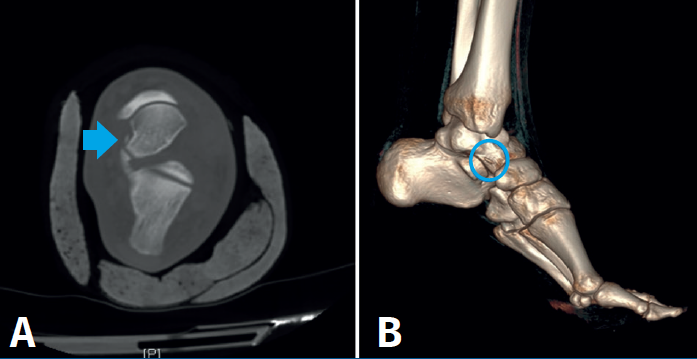

En la TC se aprecia arrancamiento óseo de 4 mm lateral a la cara externa del astrágalo, sin observar otras líneas de fractura (Figura 3).

Figura 3. A: corte axial y B: reconstrucción 3D donde se aprecia fragmento óseo de 4 mm lateral a la cara externa del astrágalo, sin observar otras líneas de fractura. Se observa una correcta congruencia articular.